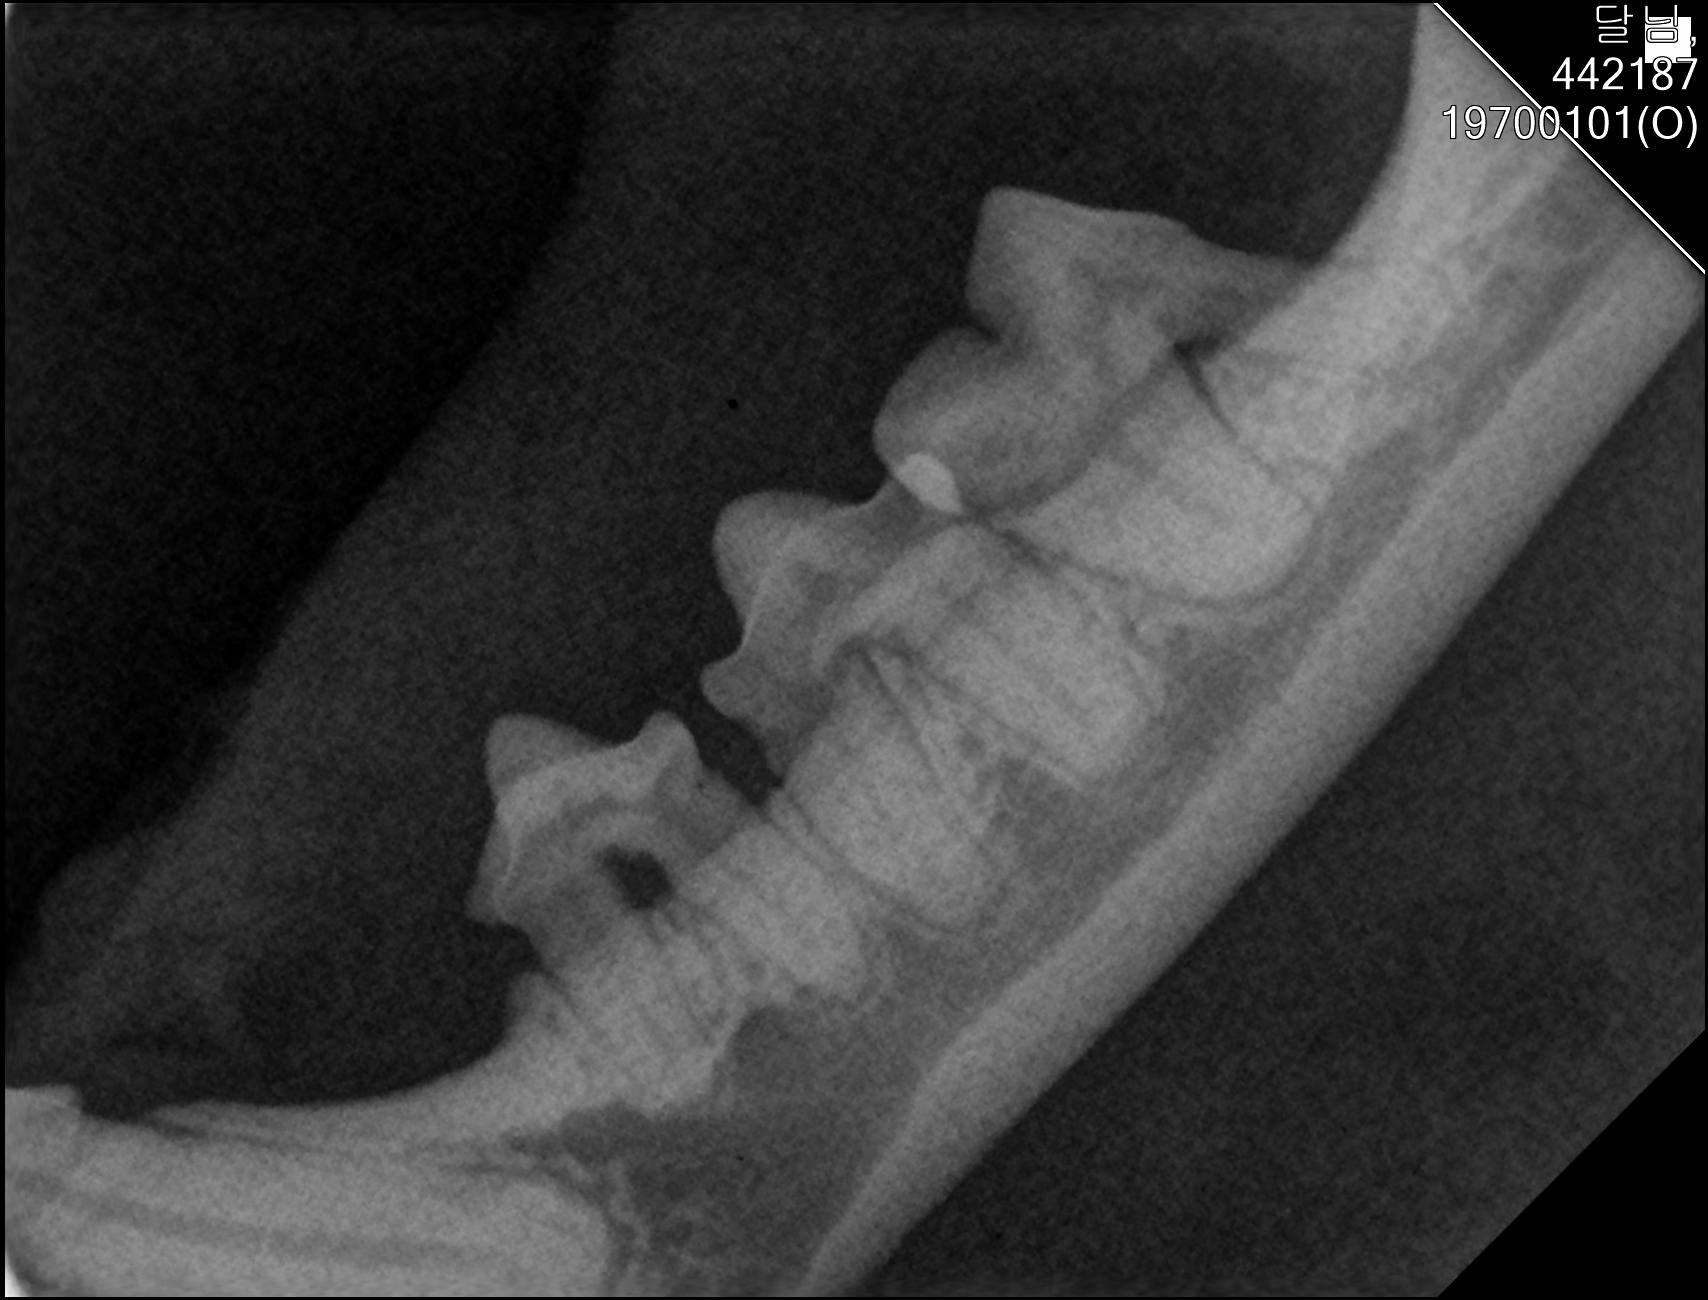

| 치료과정 | 달님이를 병원에 데려갔을때 거의 한달 가까이 먹질 못했기 때문에 몸무게는 2키로 초반대로 나갔고 마취하고 검사할수있는 상태가 아니였기 때문에 피검사를 통해서 간단히 검사후 입원하기 시작했습니다 탈수증세가 너무 심했고 수액을 맞으면서 자발식을 찾으려 했지만 달님이는 전혀 먹질 않았고 입원기간도 길어지게 되었습니다 그 와중에 청천벽력같은 소리를 듣게되었습니다 신장수치가 좋지않아 신부전이라는 결과였습니다 손도안타는 이아이를 제가 과연 케어할수있을까 너무 너무 걱정이였고 눈물이 앞을 가렸습니다 하지만 우선 체력을 회복한후 걱정은 나중에 하기로하고 달님이 치료에 집중하기 시작했습니다 병원에서도 선생님들이 달님이를 강제 급여도 해주고 수액도 계속 맞고 보니 꽉 막혀있던 코에서 콧물도 나고 소변도 보기 시작했습니다 그리고 다시 검사를 하고나니 다행히 신부전은 아니고 지방간이라고 하였습니다 아마도 오래전부터 먹는양이 줄어들었고 최근에 들어 아예 먹질못해서 간이 망가졌고 황달증세가 생겼다고합니다 어떤 이유에서인지모르겠지만 달님이는 원래 호흡기도 안좋았고 항상 콧물과 재채기를 달고산 아이라 호흡기도 안좋았고 이빨상태도 안좋아 밥을 못먹기 시작했던거같습니다 우선 체력회복이 중요하기때문에 집에서 케어한후 간 회복후 추후에 발치를 하기로 하였습니다 집에 온후 달님이는 바로 사료를 먹기시작했습니다 아마도 병원이 싫어서 밥을 안먹었던 모양입니다 매일 처방식과 약을 먹이면서 살을 찌우기 위해 이것저것 달님이가 좋아하는 캔과 츄르를 바치기 시작했고 다행히 달님이는 매일 맛있는 밥을 먹으며 살이 찌기시작했습니다 한달되는 날 발치와 검사를 위해 병원에 가서 검사를 하였는데 달님이는 3.86키로로 몸무게도 상당히 늘었으며 검사결과 모든 수치가 좋아졌습니다 그리고 마취후 이빨상태를 보니 치주염이 심각했고 이빨은 어금니부터 송곳니까지 다 내려앉은 상태였습니다 입안은 구내염이 시작되었고 원장님은 송곳니도 지금도 안좋지만 나중에 되면 더 아퍼질꺼라며 전발치를 해야한다 하였고 저는 달님이과 전발치를하고 길에서 잘 살수있을까 너무 걱정이였지만 나중에 아파서 또 구조후 마취하는것보다 낫다고 생각했고 밥자리도 잘 되어있어 전발치하고도 잘사는길냥이들 많다고 들어서 전발치를하게되었습니다 달님이는 수술을 잘 마쳤고 퇴원후 달님이는 집에서 10일정도는 약먹고 회복해야하기때문에 집에서 좀더 케어한후 방사할 예정입니다 |